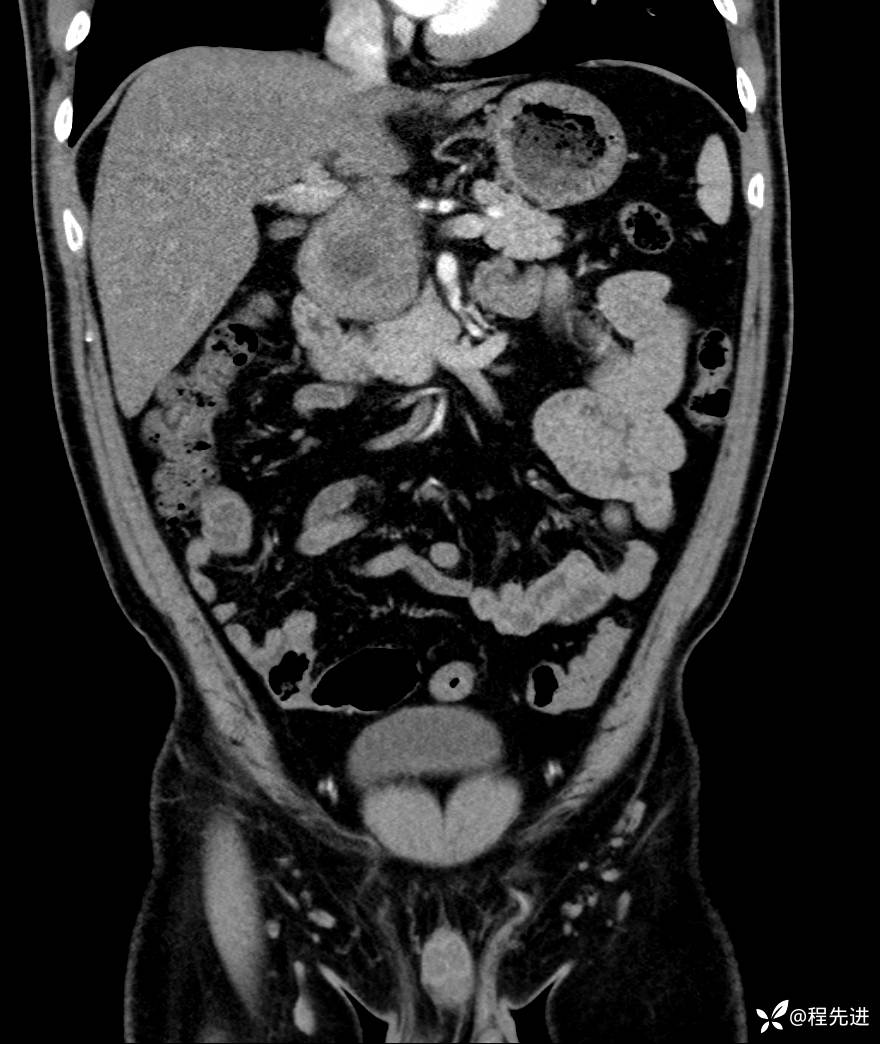

【腹盆】特别精彩病例|发现腹膜后肿物1月余

主诉:发现腹膜后肿物1月余

现病史:患者1月余前查体,行超声检查提示:后腹膜囊实性肿块;慢性胆囊炎伴胆囊内结石;无腹痛腹胀,不伴腹泻发热等;偶感腰背部酸痛。

CT平扫+增强: